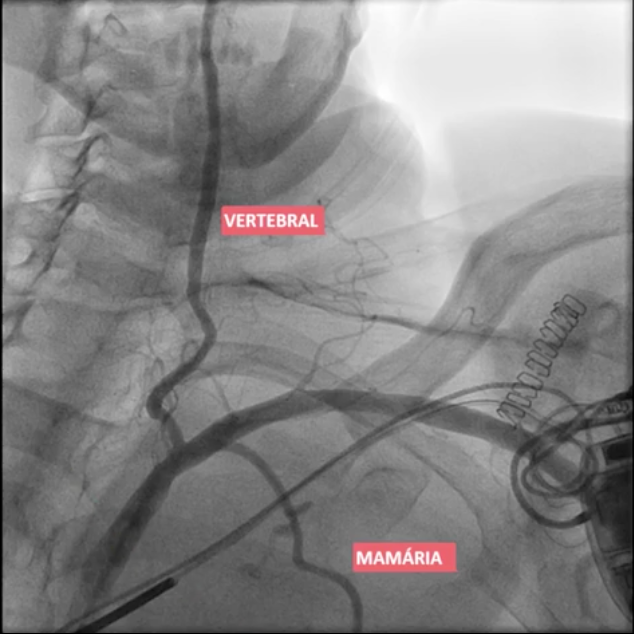

Roubo da subclávia

Obstrução proximal da subclávia com inversão de fluxo da vertebral e da mamária para irrigar o braço;

Restaurar o fluxo da subclávia:

-Endovascular com stent

ou

-Aberto: enxerto carotídeo subclávio